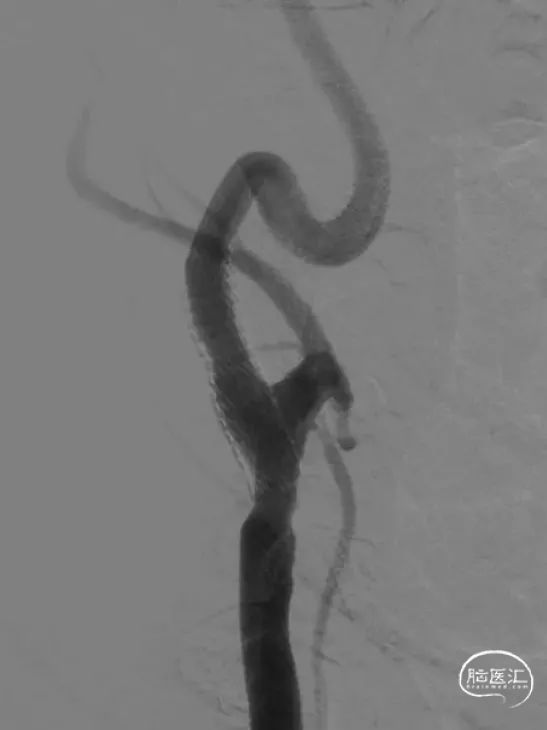

左侧颈内动脉起始段重度狭窄

左侧颈内动脉颅内段充盈明显延迟